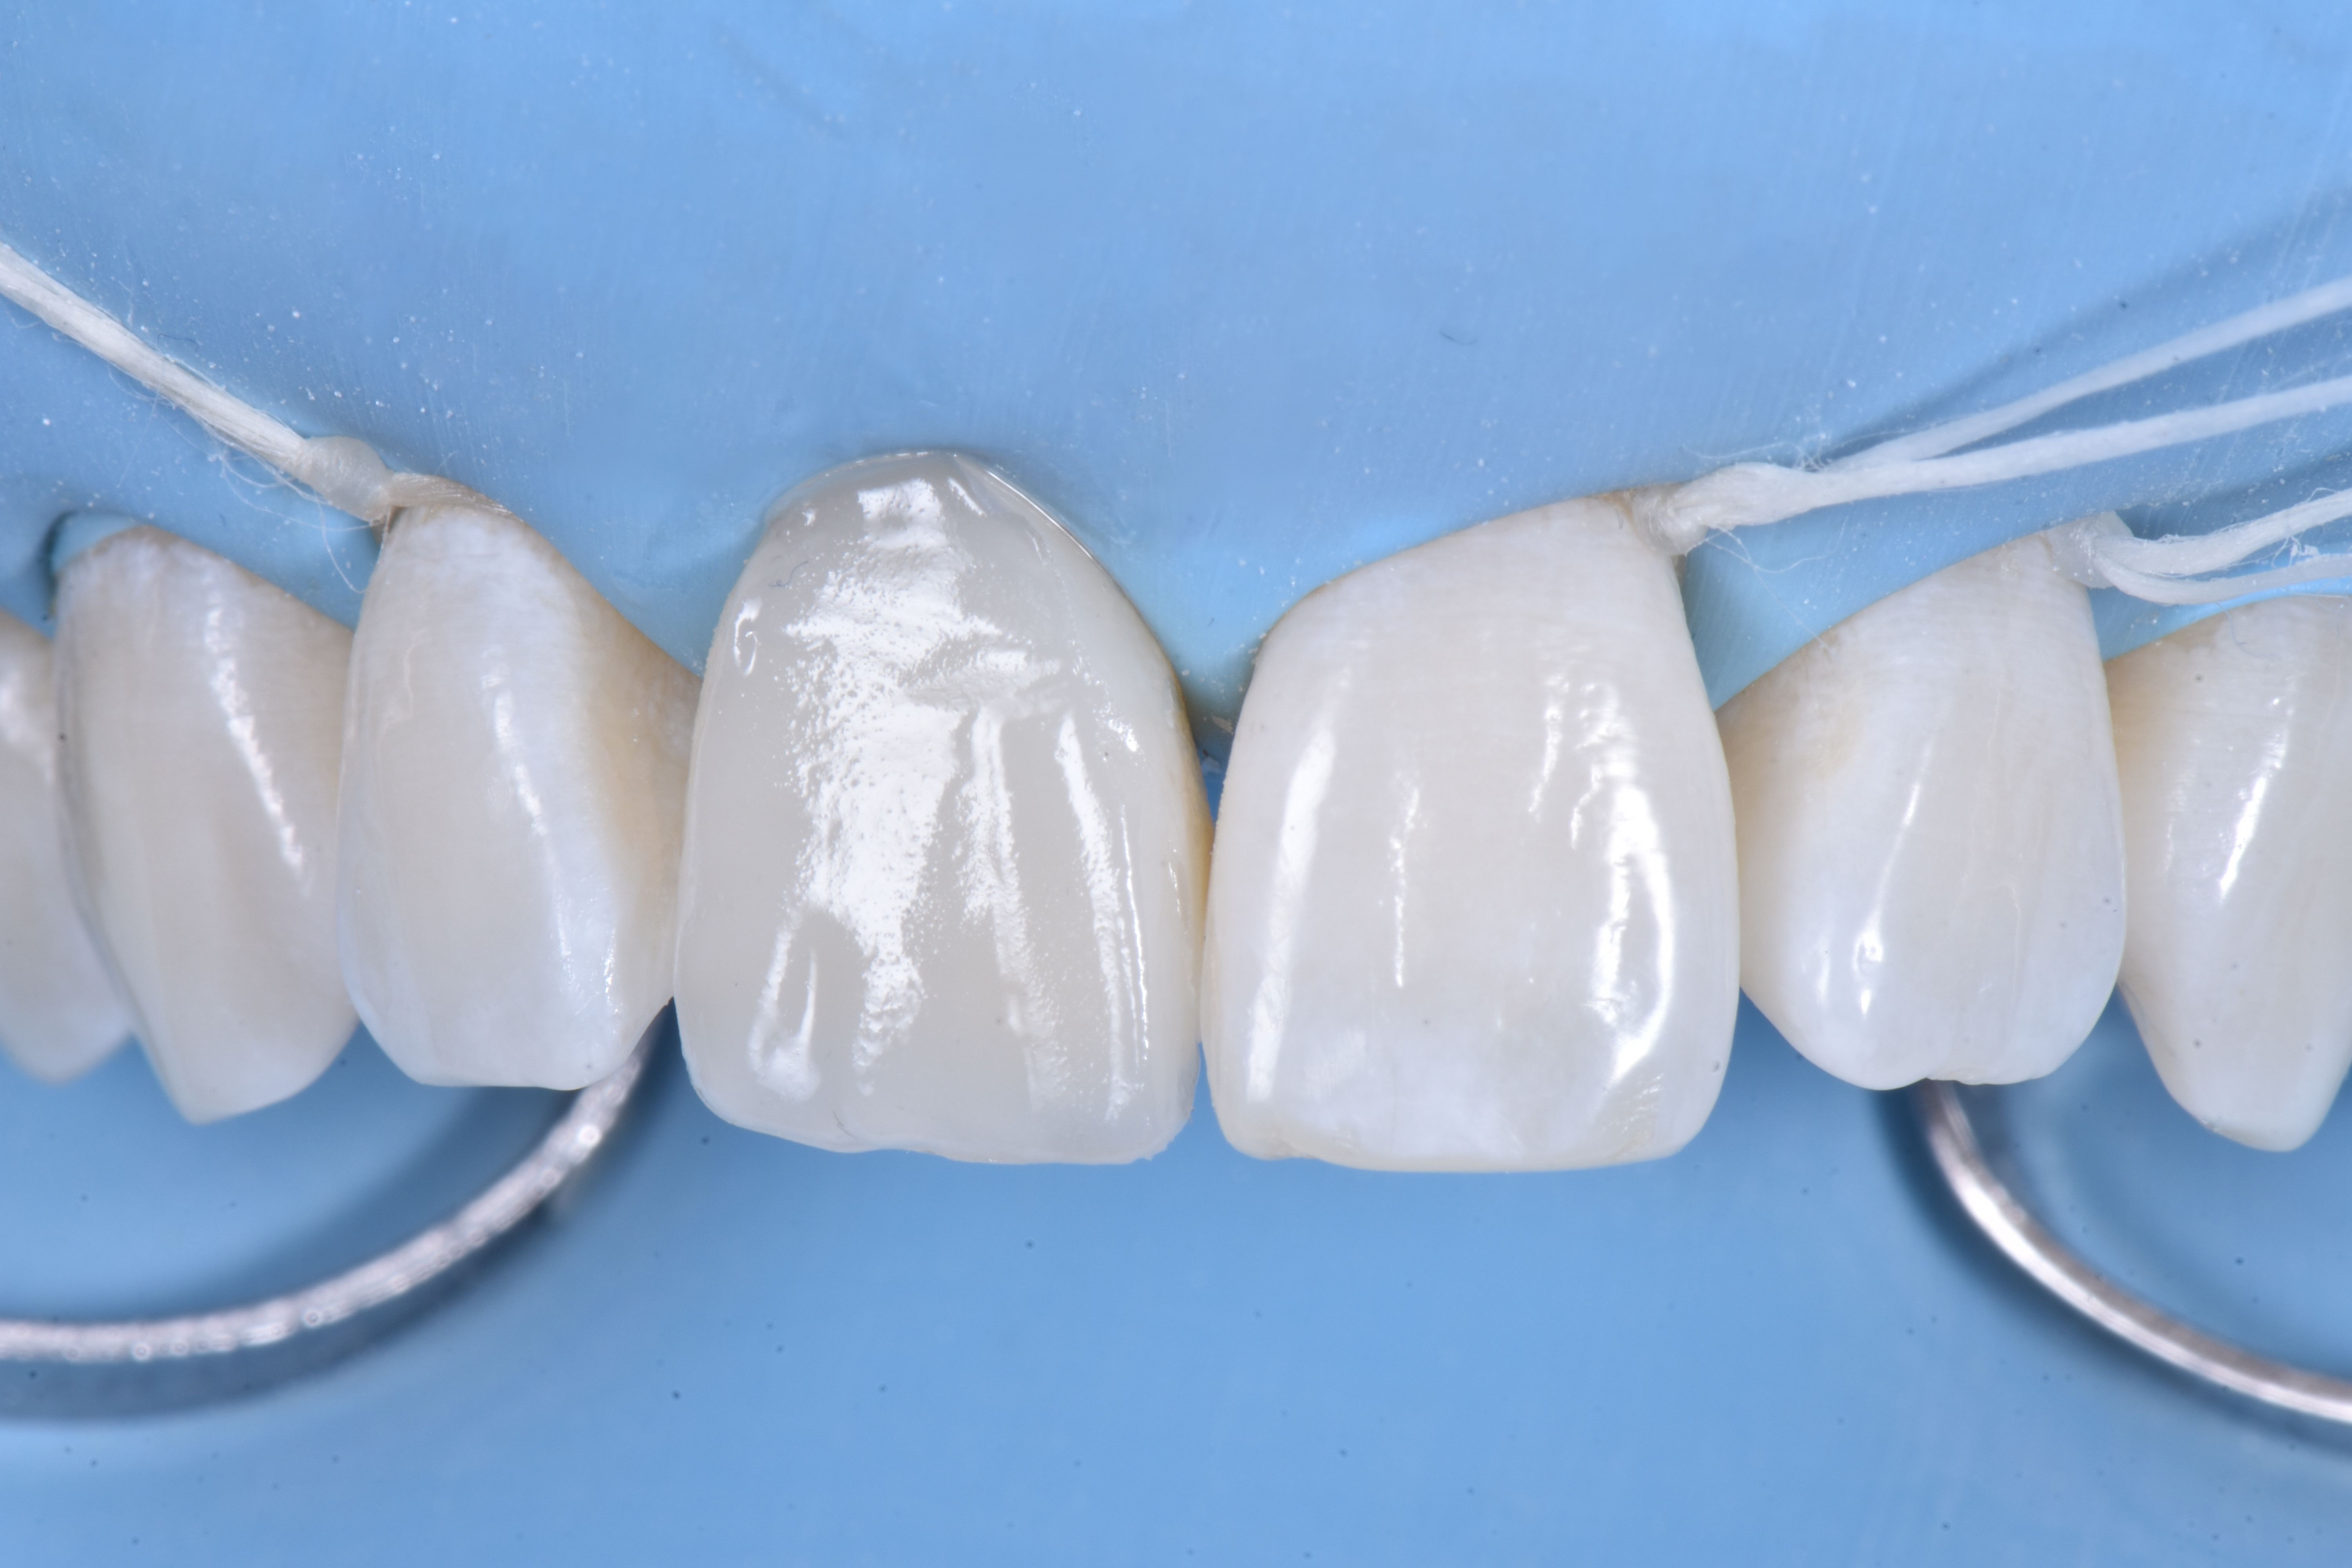

Jasnoniebieskie i białe odcienie (ESTELITE COLOR firmy TOKUYAMA DENTAL) zastosowano w celu odtworzenia opalescencji w obszarze siecznym (ryc. 10).

Odbudowę uzupełniono poprzez zastosowanie odcienia szkliwnego (ESTELITE ASTERIA WE firmy TOKUYAMA DENTAL) w postaci jednej warstwy. Powierzchnię przedsionkową wymodelowano i skontrolowano w każdym wymiarze, aby jak najmniej trzeba było ostatecznie korygować. Następnie spolimeryzowano w ciągu 20 sekund, a potem przez 40 sekund od strony przedsionkowej i podniebiennej po pokryciu żelem glicerynowym w celu uniknięcia powstania warstwy inhibicji tlenowej kompozytu (ryc. 11).